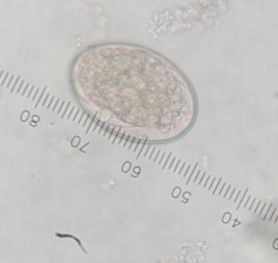

วัดความรู้ว่ารู้จักไข่พยาธิแค่ไหน